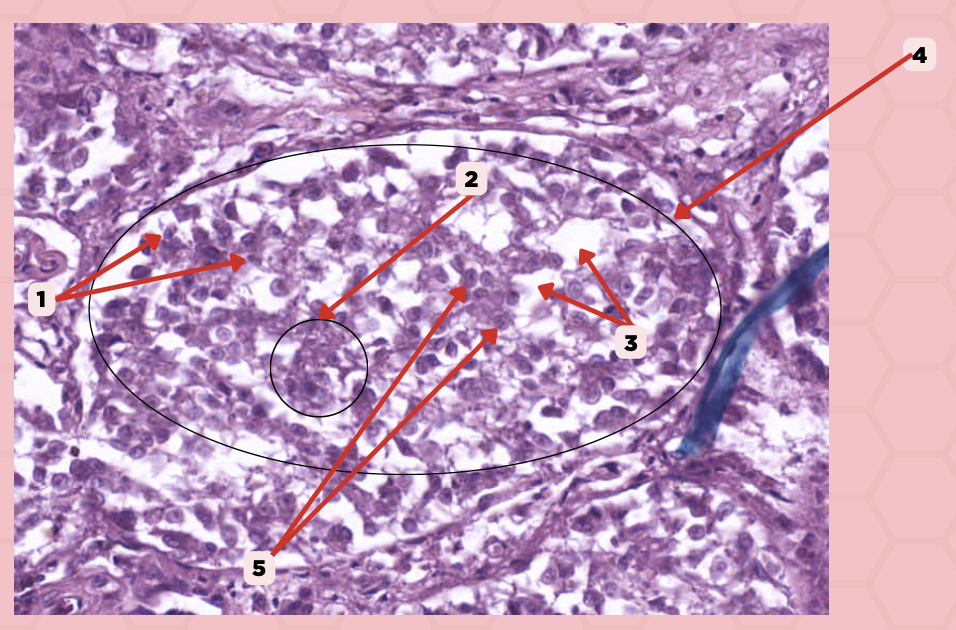

Identify the specimen.

Lobule

Identify the structure labeled as 1.

#5 Pinealocytes (Chief Cells)

Which among these structures are modified neurons that are responsible for synthesizing melatonin?

#1 Interstitial Cells

Which among these are supporting cells that are morphologically similar to astrocytes?

Interstitial Cells

Identify the structure labeled as 1.

Clusters (Cords) of Cells

Identify the structure labeled as 2.

Capillaries

Identify the structure labeled as 3.

Lobule

Identify the structure labeled as 4.

Pinealocyte

Identify the structure labeled as 5.